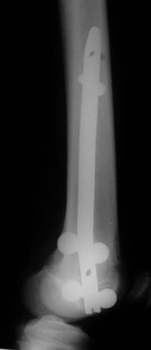

Retrograder Nagel

Oberschenkelfraktur bei einem 17-jährigen

postoperativer Befund |

belastbar nach 8 Tagen